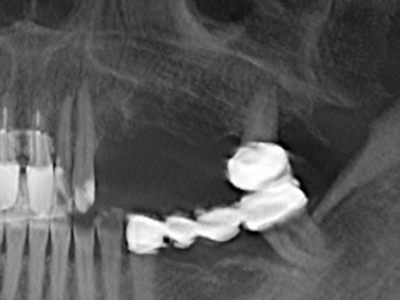

Indication: Bone splitting

Bone tissue is not simply a mineral structure but also contains a substantial proportion of collagen fibres. This means it not only has good compressive strength but also a degree of flexibility, which can be taken advantage of when performing bone augmentations. In the classical expansion procedure using bone splitting, the atrophied alveolar ridge is split longitudinally and carefully expanded after reaching an adequate osteotomy depth (Fig. 13-16), ideally without substantial removal of the periosteum (Brugnami, Caiazzo et al. 2014, Stricker, Fleiner et al. 2014). Screw and plate systems with increasing expansion distance have proven effective in separating the two bone lamellae while remaining below the fracture threshold. In general, residual bone widths of at least 3–4 mm are required (Chiapasco, Zaniboni et al. 2006) to guarantee adequate flexibility and sufficient bone coverage of the future implants. If necessary, a vertical relief osteotomy on one or both sides can improve flexibility. A combination with additional augmentation techniques, particularly on the buccal side, has been described as an alternative to the classical technique.

The splitting procedure is particularly atraumatic and there is no significant loss of dimension when using piezosaws, and there are no significant differences between implants in split jaws and implants in an alveolar ridge without a bone deficit (Chiapasco, Zaniboni et al. 2006, Danza, Guidi et al. 2009). However, sufficient continuous irrigation is essential, particularly with locally restricted and deep splitting to prevent thermal stress in the apical osteotomy regions.